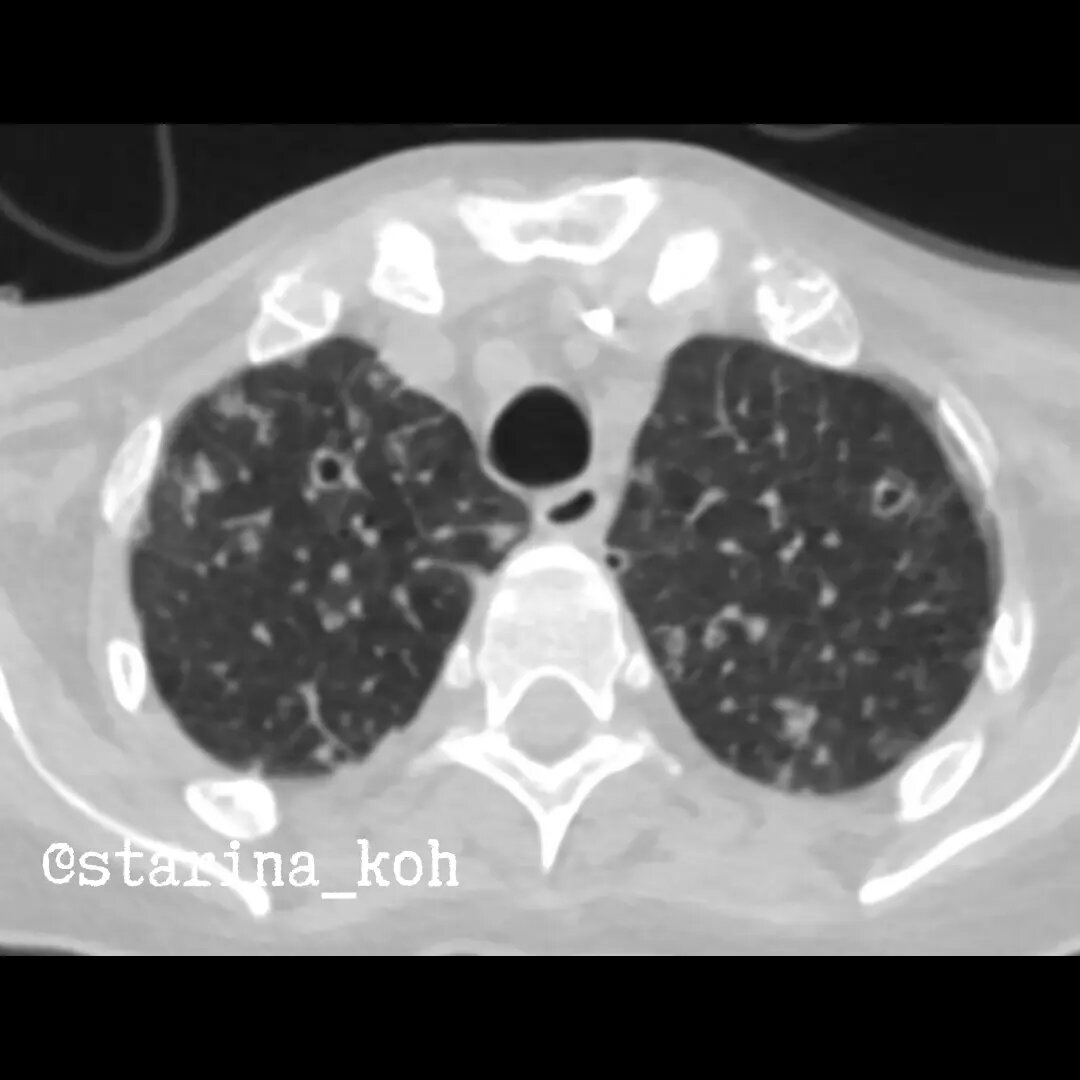

Септическая эмболия

Наблюдательные читатели могут сказать - Старина, вы подсунули нам РГ и КТ разных больных. Постойте, сейчас все объясню (с). На самом деле - снимки одного пациента, но с разницей 6 дней - мы видим распространенные изменения на КТ, которых на РГ еще нет, за исключением единичных элементов - а мы понимаем, что они бы так или иначе "попали" на снимок. Имеем дело с очень бурным процессом!

Именно тогда, перед интубацией и была выполнена КТ - мы видим, что в лёгких имеется большое количество хаотично расположенных очагов, часть из которых с распадами, а также мелких полостей, инфильтратов и участков инфарктов в базальных отделах - вся эта КТ-картина в совокупности с тем, что изменения почти полностью отсутствовали 6 дней назад свидетельствует в пользу септической эмболии лёгких - часто очень бурно протекающему процессу, сопутствующим сепсису с наличием гнойного источника в организме - а их у пациентки было диагностировано минимум два - именно оттуда и "летят" инфицированные тромбы в окружающих сосудах, и далеко не только инфекционный эндокардит может стать причиной такой эмболии. В чем сложность данного случая? В наличии у пациентки онко анамнеза - если бы мы увидели подобную картину при поступлении на КТ (не зная о клинической картине) - можно было вполне думать и о метастазах колоректального рака в легких - ведь кавитирующие (т.е. полостные) метастазы - не такая уж и редкость. А если сочетание процессов? В общем, в данном случае именно корреляция клинической картины и изменений на КТ в виде быстрой отрицательной динамикой, а также характерных двусторонних элементов разного вида (очаги, инфильтраты, распады) позволило думать о том, что у пациентки септическая эмболия лёгких в рамках генерализованного сепсиса - уже на аутопсии удалось получить рост из материала легких acinetobacter spp., Klebsiella pneumoniae, Ps. aeruginosa.